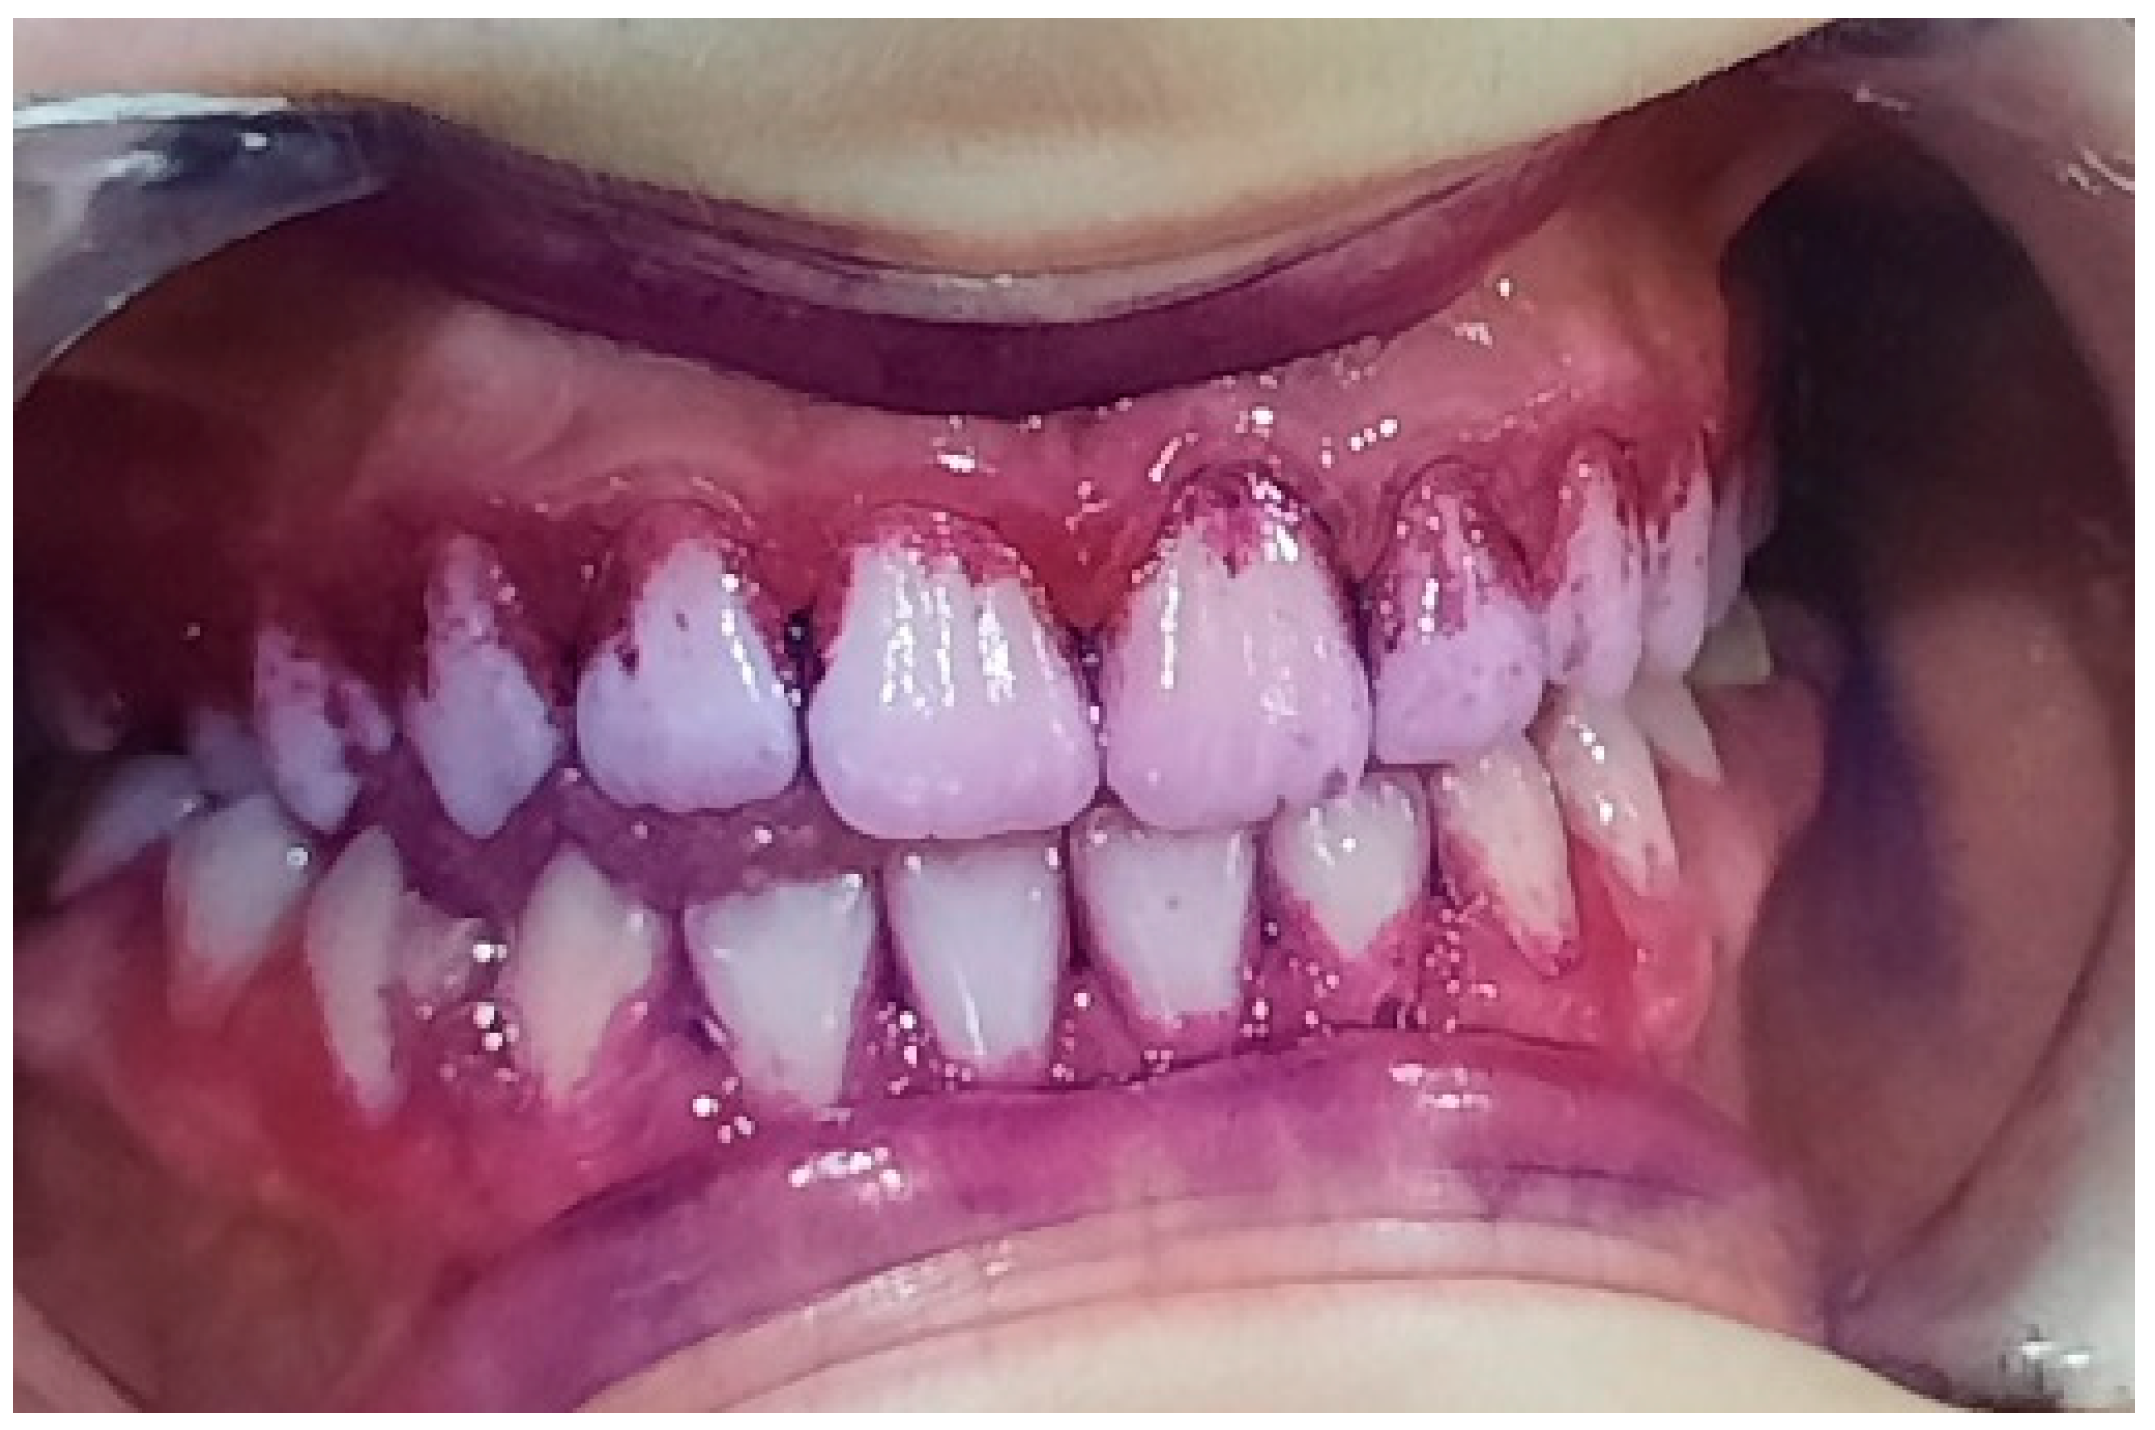

2.2. Clinical Examinations

3.2. Analysis of Clinical Data